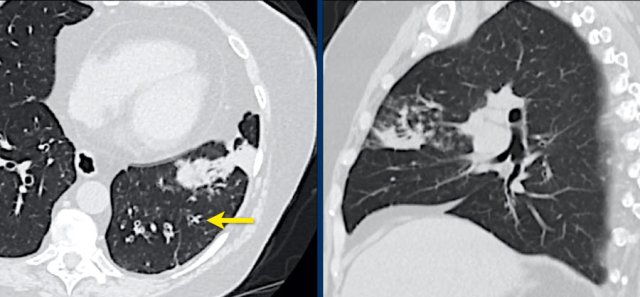

Patient with positive PCR and bilateral GGO.

Notice halo sign (arrow).